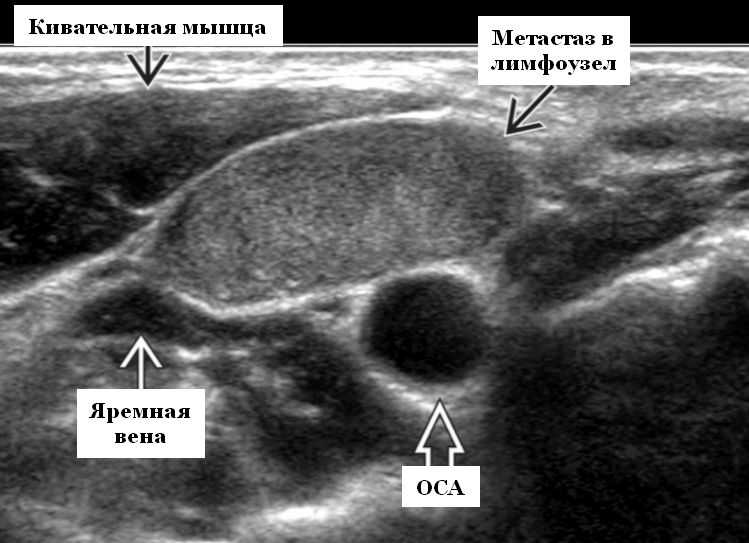

Рис. 4. Кот до сеанса химиотерапии. Видно заполнение легких жидкостью по причине лимфомы средостения.

Рис. 5. Тот же пациент через 7 дней, после сеанса химиотерапии. Отчетливо видны улучшения, лимфома средостения не визуализируется.